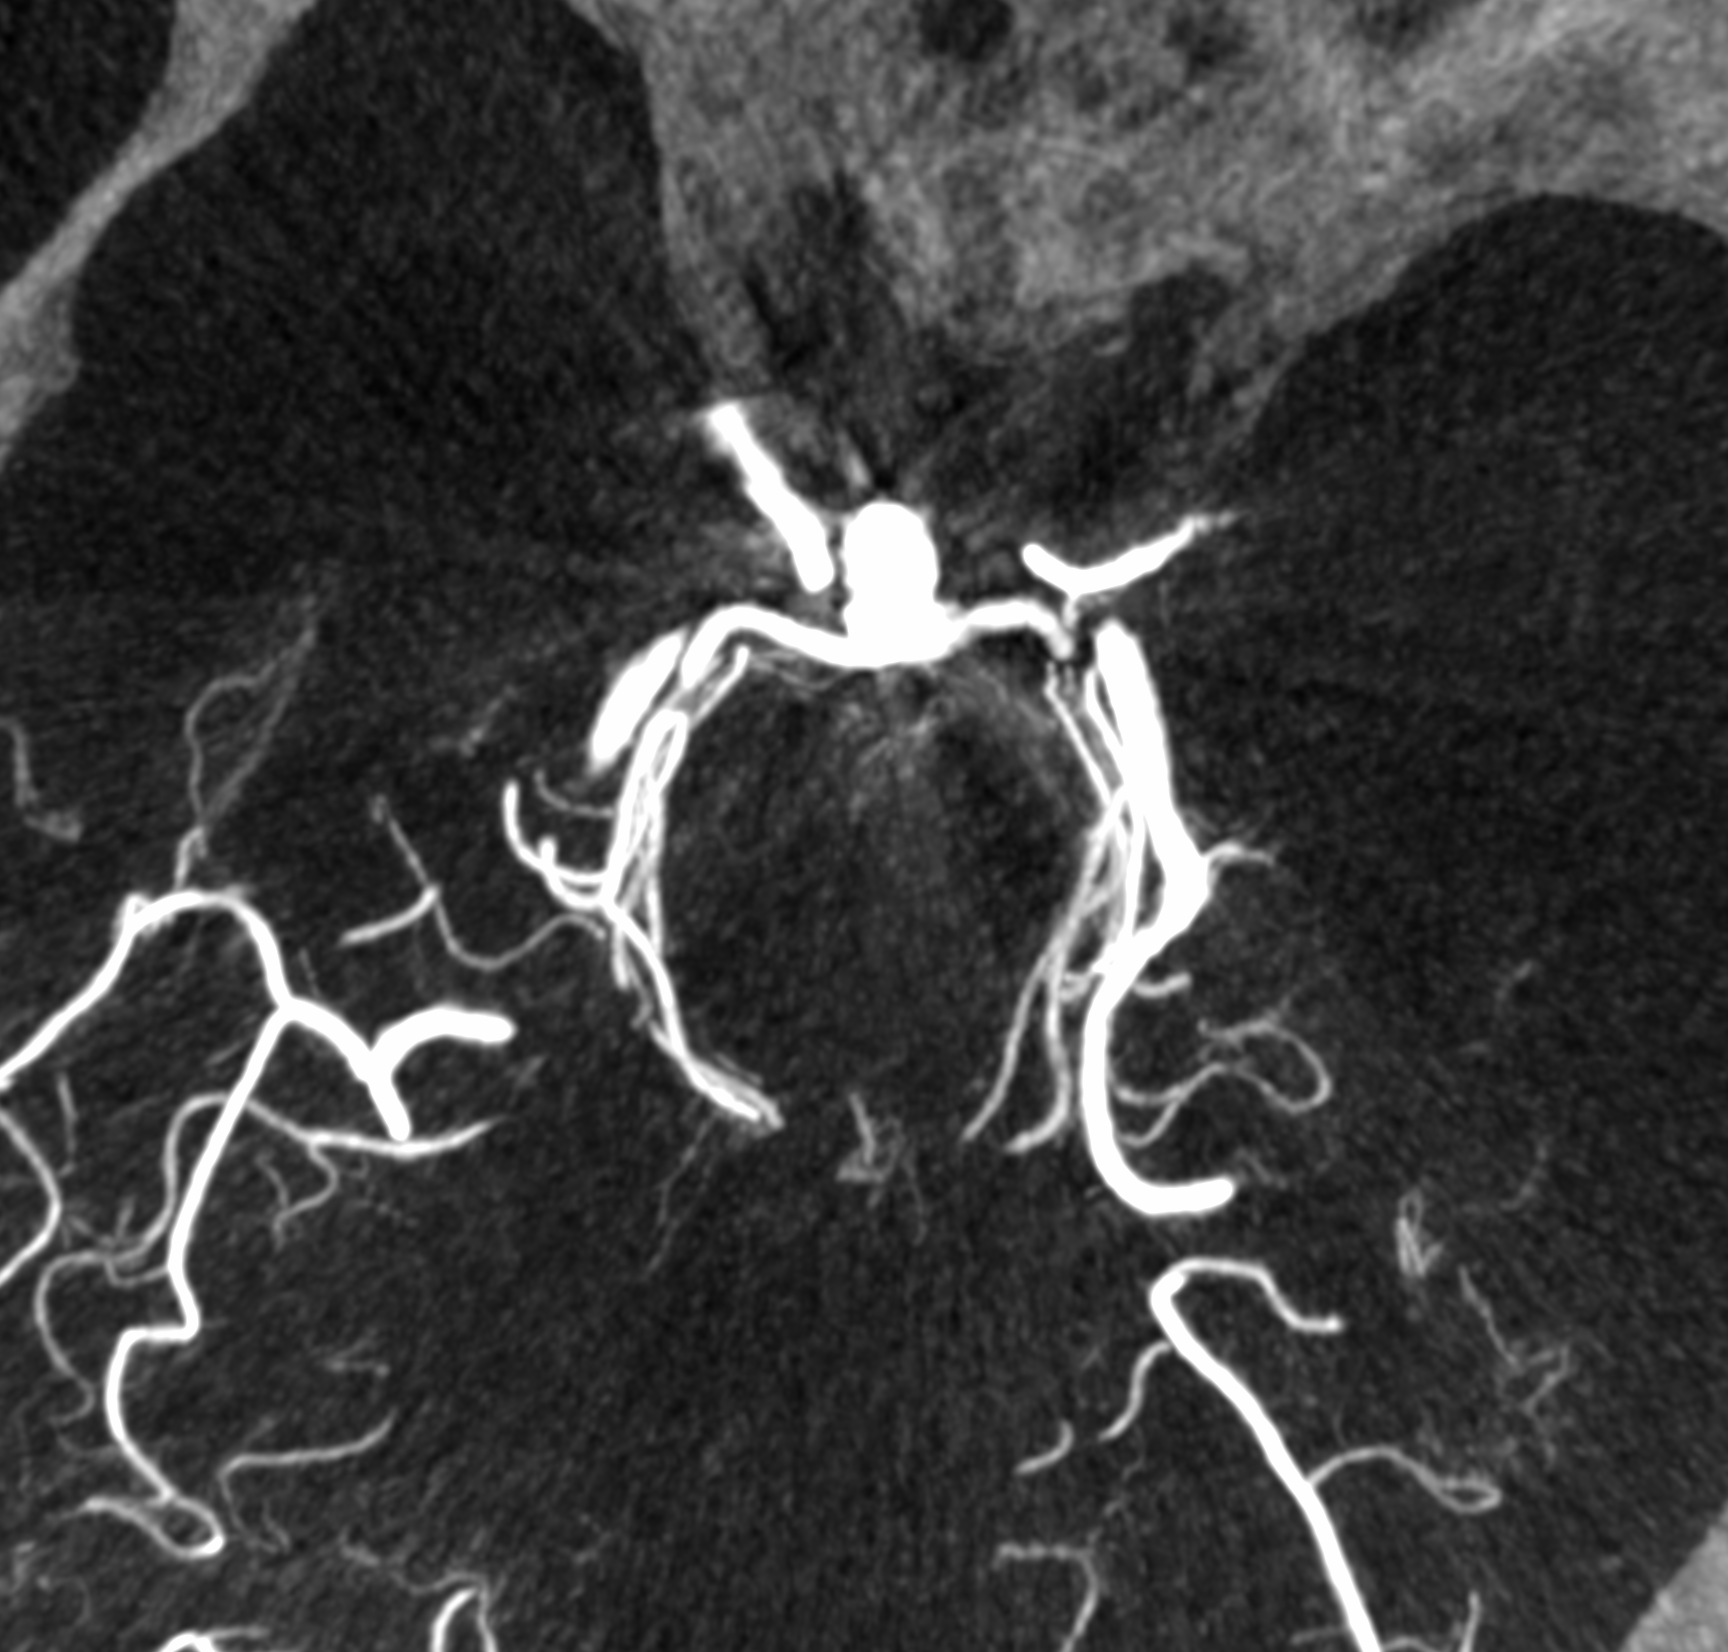

Converting DICOM images of cerebral aneurysms into STL format for 3D printing is a complex process. We faced the task of software development that would facilitate STL file preparation for cerebral aneurysms. Vessels segmentation (segmentation of vascular system in general) is highly time-consuming, however, thanks to our internal RnD projects we managed to propose an algorithm that performs it automatically.

Medical evaluation of segmentation accuracy was positive. Mesh of micro-triangles with vessel diameter being up to 5 [mm] – built upon this segmentation – was an input to the further steps. Each of them is described in detail in separate posts, below you may find general descriptions and links.

The task was to automatically connect the inflows and outflows of a segmented 3D model of a brain aneurysm to points in well-defined location 3D space to produce a physical 3D printable model. We began by calculating the model’s centerlines, which provided us with information about the presented mesh, such as diameters along the centerline points. The mesh was then divided into separate branches so that we could determine which part of the mesh was an aneurysm and which part was a model ending. Then we proceeded to the automatic connection optimization phase, where we decided which point to use for cutting the branch and connecting it to the 3D point in space. As a result, we successfully created automatic and seamless connections for the brain aneurysm mesh.